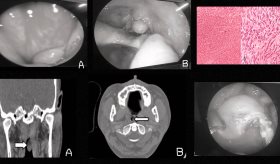

Diagnóstico y examen físico

El examen físico se centrará en revisar el esternón para detectar sensibilidad o hinchazón. Asimismo, se pueden dirigir movimientos de la caja torácica o de los brazos para desencadenar los síntomas.

Dado que los síntomas de esta afección son similares al de las enfermedades cardíacas, pulmonares, problemas gastrointestinales y la osteoartritis, dependiendo el riesgo de cada caso, se pueden realizar exámenes para descartarlas, como un electrocardiograma o radiografía de tórax.